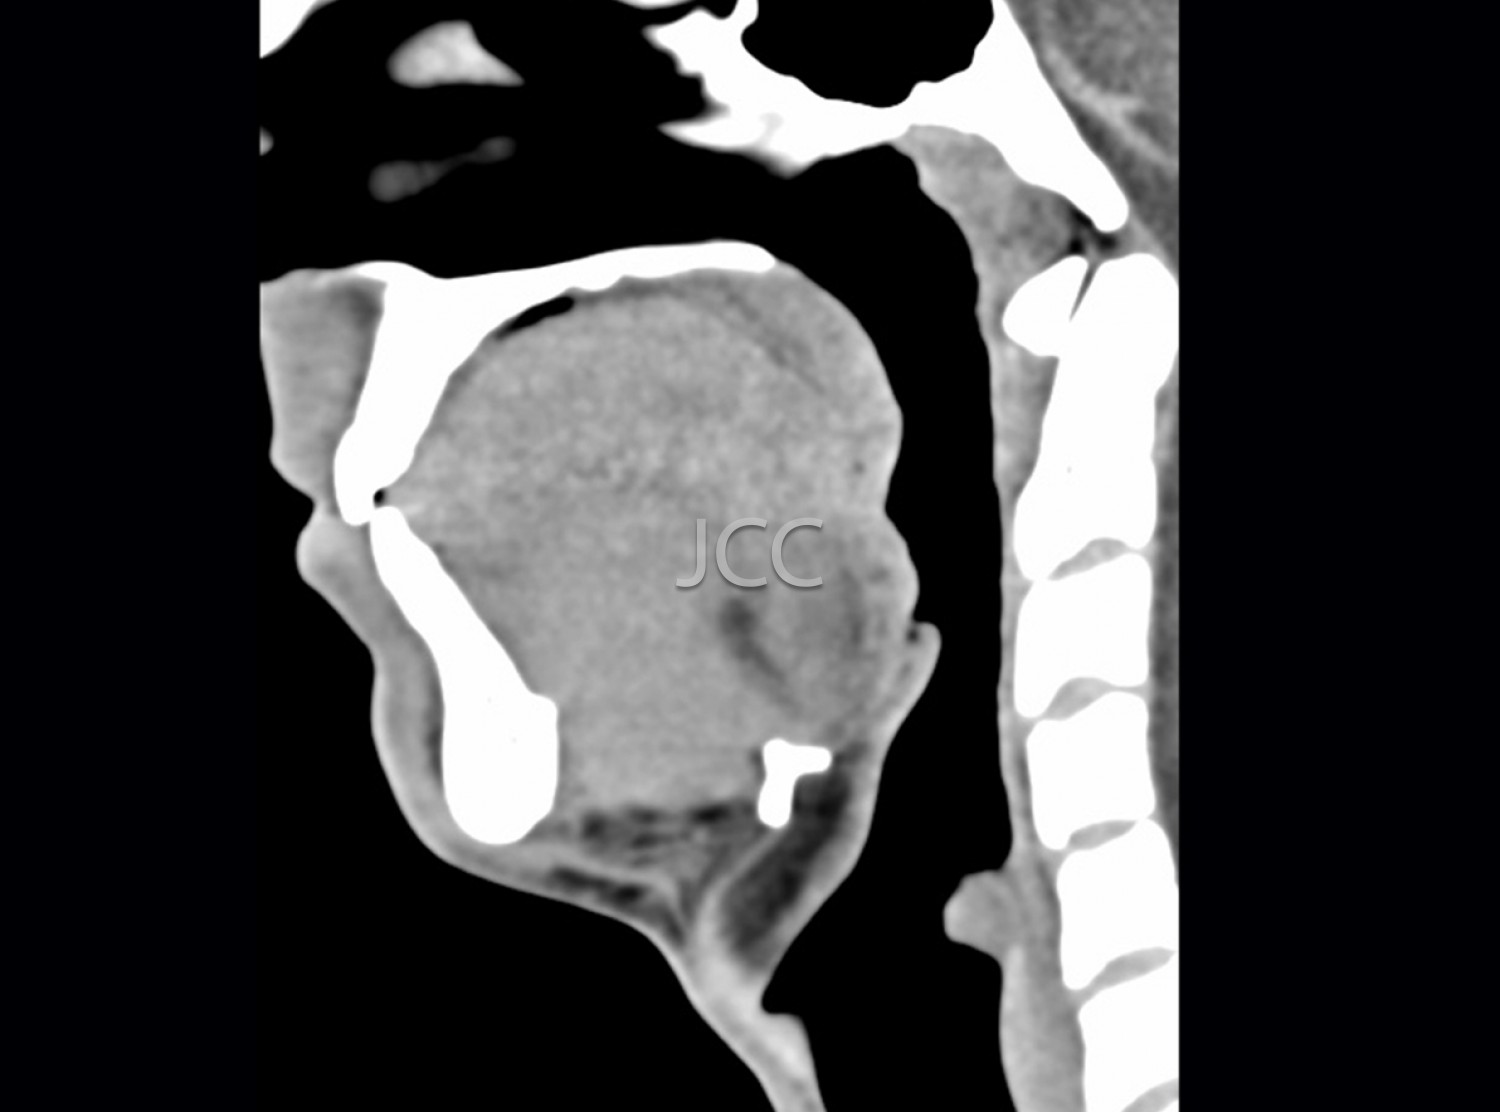

Tomografia Axial Computorizada - TAC Cavum

A Tomografia Axial Computorizada (TAC) - Dupla Energia - 256 cortes é uma técnica de diagnóstico que permite a avaliação de várias partes do corpo humano, incluindo pulmões, fígado, pâncreas, rins, coração, estruturas vasculares e estruturas ósseas.